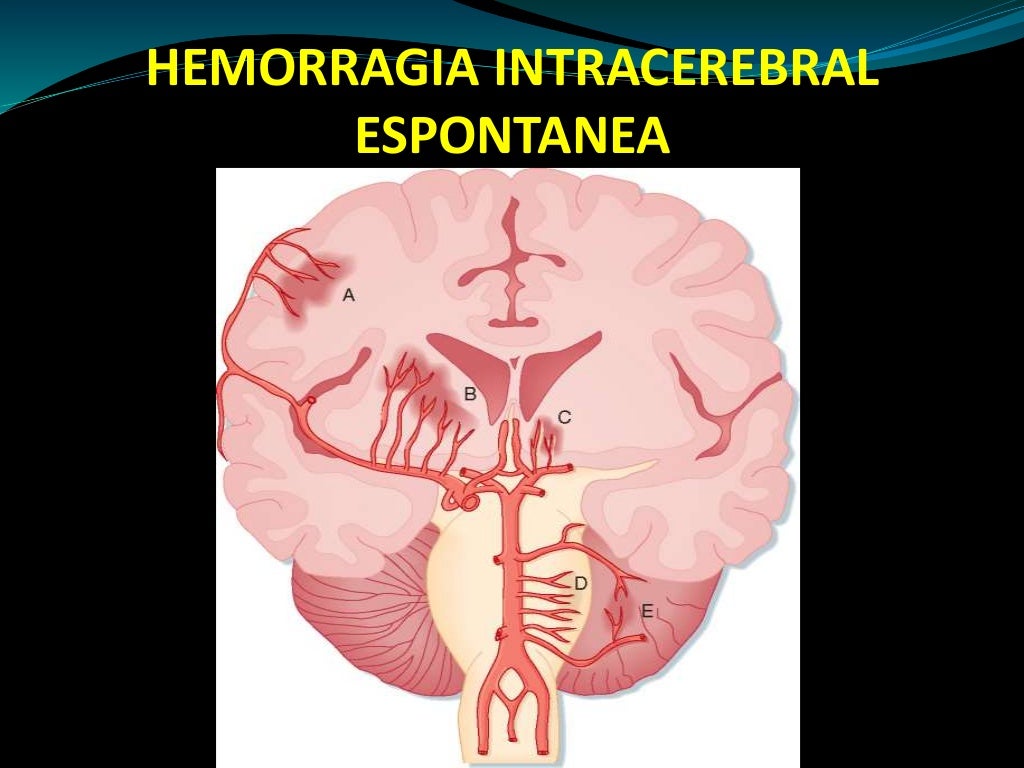

hemorragia cerebral Puede deberse a un trauma cerebral. The following 2 files are in this category, out of 2 total. Media in category intracerebral hemorrhage. La causa suele ser la hipertensión. Puede ser externo o dentro del cuerpo. Como ya se ha mencionado, suele estar relacionada con la hipertensión. Un hematoma intracraneal es una acumulación de sangre dentro del cráneo. En general, se distinguen entre hemorragias profundas (incluyendo aquellas que afectan a núcleos grises profundos de los hemisferios cerebrales), hemorragias.

Hemorragia Intracerebral subraquídea Neurocirugía de la Torre

Diagrama que muestra hemorragia cerebral humana. 434335 Vector en Vecteezy